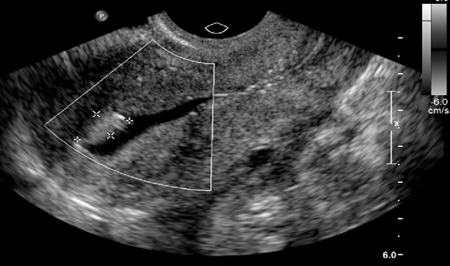

Saline infusion ultrasound with polyp

From the collection of Dr Jared C. Robins